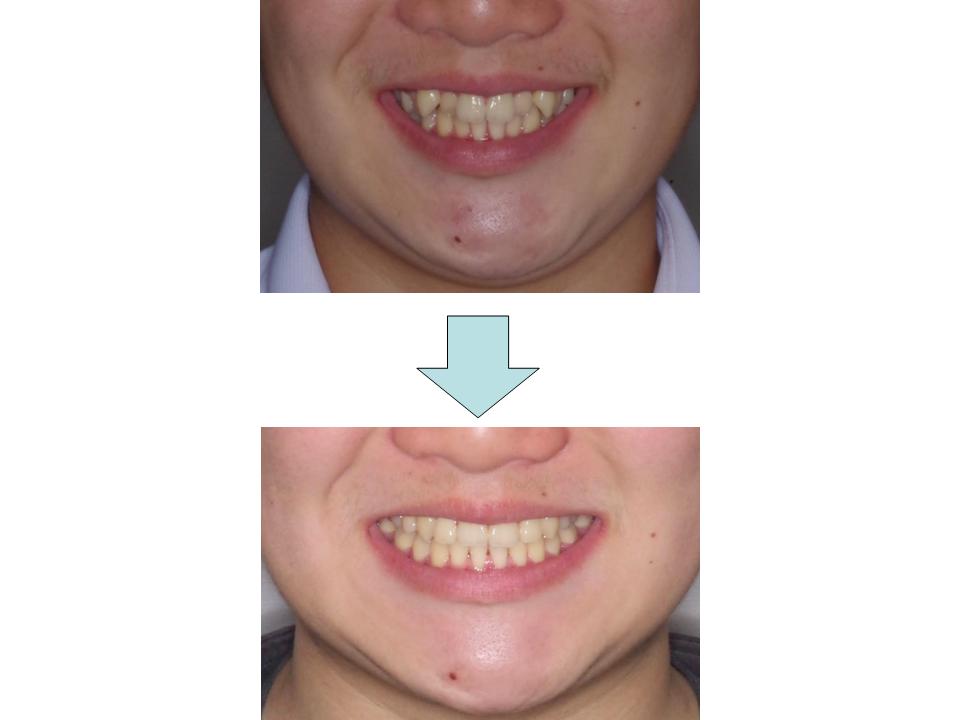

下の歯のガタガタ、口元の突出感

下の歯ならびが前方に出ていることに起因したかみ合わせの不正であることから、下の前歯の凸凹の改善と、上下の奥歯の位置修正のために上下異なる部位の抜歯を行い、舌癖の改善訓練と併せた治療を行いました。結果として良好なかみ合わせとなり、口元の改善もできました。

| 主訴 | 下の歯のガタガタ、口元の突出感 |

| 年齢・性別 | 22歳 / 男性 |

| 抜歯部位 | 上顎両側第二小臼歯、下顎両側第一小臼歯 |

| 装置 | メタルブラケット |

| 期間 | 2年6か月 |

治療前

治療中

治療後

治療費790,000円

通院回数30回